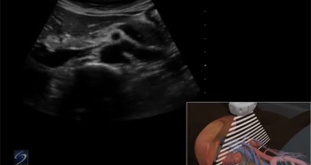

3D How To: Right Kidney Ultrasound 2224